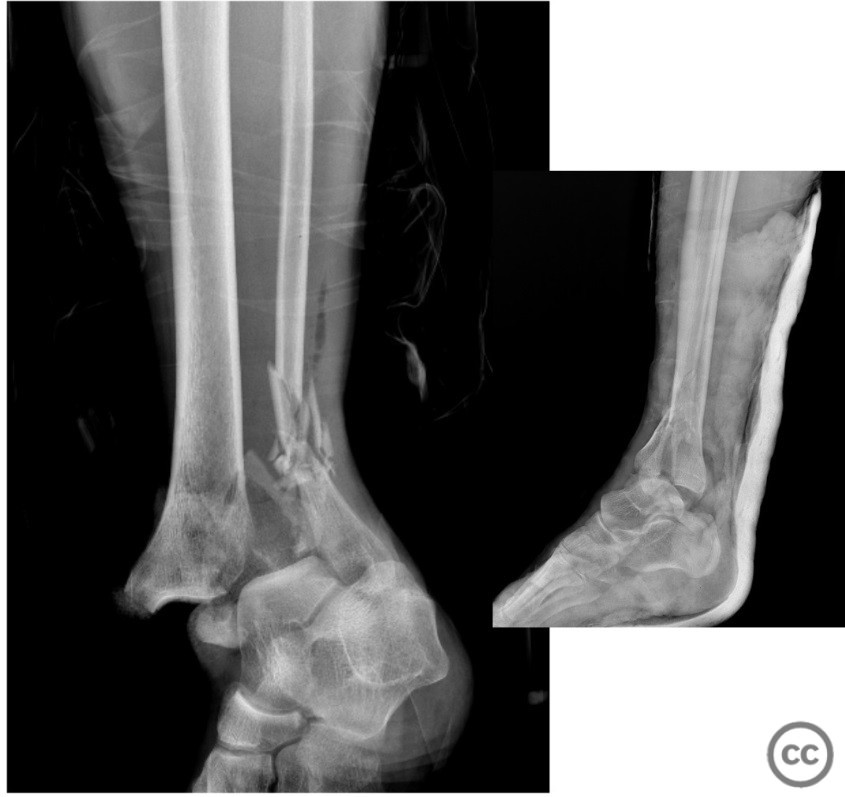

Open Medial Malleolus Fracture-Dislocation with Tibial Pilon and Lateral Malleolus Fractures

Clinical and radiological findings:  A 57-year-old male presented to the emergency department following a fall from a height, sustaining a medial malleolus type 2 open fracture-dislocation, a tibial pilon fracture, and a lateral malleolus fracture. The neurovascular examination was normal. The patient arrived at the emergency room within 30 minutes post-injury. Prophylactic antibiotics were administered promptly. Initial wound debridement and closure were performed in the emergency department, followed by a CT scan prior to urgent surgical intervention.